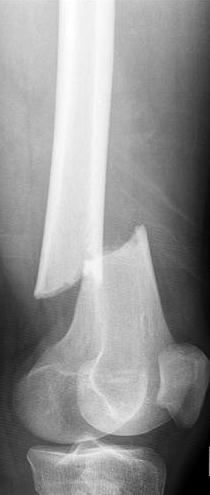

Some studies have shown that long-term use of bisphosphonates may actually weaken bones over time, leading to femur fractures, jaw damage, and other joint breaks.